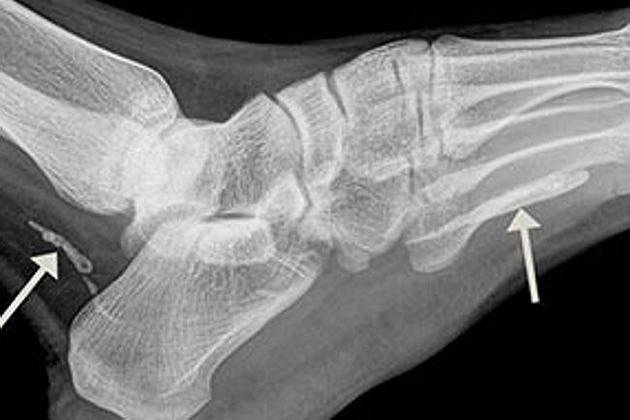

Gambar Sinar X Menunjukkan Cacing yang Bersarang di Kaki (Fairfax Media)

Awalnya, pria Sudan ini khawatir terjadi sesuatu pada kakiknya. Sebab, ia merasa ada sesuatu yang bersarang di kakinya. Fakta mengejutkan tersebut akhirnya terungkap melalui sinar X. Dua potong 'spagheti' berbentuk cacing Guinea bersarang di bawah betis dan kaki. Dokter menyatakan, mungkin makhluk tersebut sudah berada di sana selama bertahun-tahun.

Meskipun memiliki kemampuan untuk tumbuh ke ukuran besar, dua cacing ini hanya bertambah beberapa senti saja. Terlebih, cacing ini telah mati dan turun ke telapak kaki. Meskipun tidak ada pengobatan untuk kasus ini, parasit cacing yang kerap ditemukan di Sudan Selatan, Ethiopia, Ghana dan Chad ini tak menular.